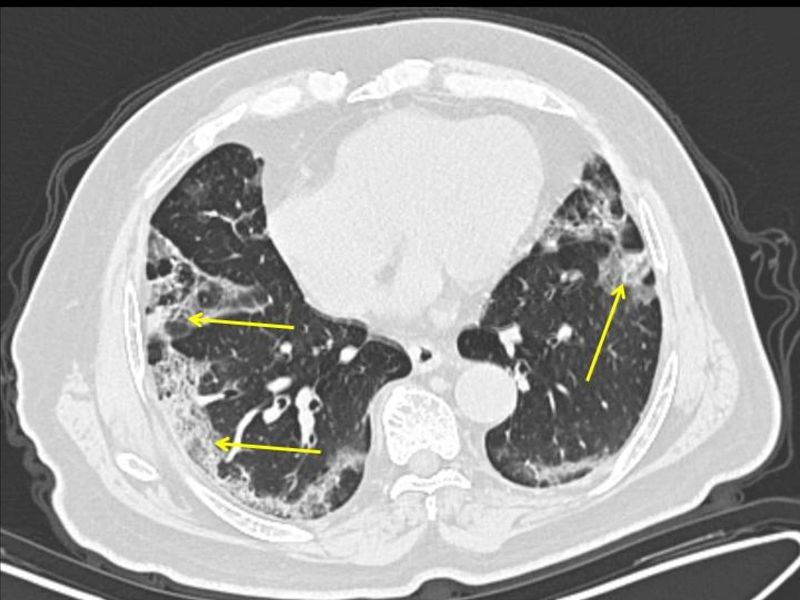

Hình ảnh chụp CT cho thấy Covid-19 tấn công phổi người bệnh (ảnh: Bloomberg)

“Hình ảnh lâm sàng cho thấy Covid-19 không giống với những gì chúng ta thấy ở bệnh cúm. Covid-19 có thể lây lan qua việc tiếp xúc với những giọt chứa đầy virus bắn ra khi ho, hắt hơi hoặc từ hơi thở của người nhiễm bệnh”, ông Jeffery K.Taubenberger người đã nghiên cứu về sự lây nhiễm của bệnh cúm ở Tây Ban Nha, cho biết.

“Sự nhiễm virus thường bắt đầu từ mũi. Khi vào trong cơ thể, Covid-19 xâm chiếm các tế bào biểu mô tuyến bảo vệ đường hô hấp. Nếu Covid-19 chỉ xâm nhập ở khu vực đường hô hấp trên (mũi, họng), nó sẽ ít nguy hiểm hơn.

Tuy nhiên, khi virus tràn xuống khí quản và mô phổi, tình trạng sẽ ngày càng trở nên nghiêm trọng. Covid-19 sẽ gây tổn thương trực tiếp tại phối kèm theo những ảnh hưởng thứ phát do phản ứng bài dịch của cơ thể”, ông Taubenberger, lãnh đạo Viện Dị ứng và Bệnh truyền nhiễm Quốc gia tại thành phố Bethesda, bang Maryland (Mỹ), cho biết.